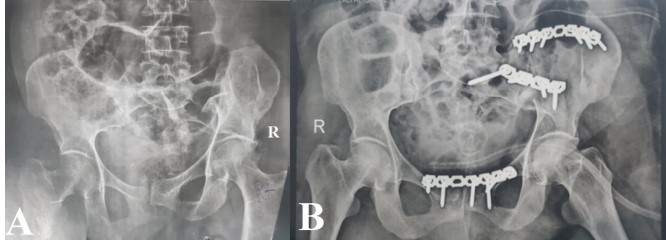

Methods: This prospective cohort study was conducted at the Military General Hospital and Al-Thawra Modern General Hospital in Sana’a, Yemen, between April 2019 and April 2023. We enrolled 76 patients aged 16– 60 years with unstable pelvic ring fractures that required surgical intervention (Tile type B/C). Data on patient demographics, mechanism of injury, fracture classification (Tile and Young-Burgess), surgical approach, and complications were collected and analyzed. Anatomical reduction was assessed using the Matta and Tornetta criteria, respectively. Functional outcomes were evaluated using the Majeed scoring system at a mean follow-up of four years.

Results: The mean patient age was 34 years, and the majority of patients were male (68.4%). The most frequent mechanisms of injury were motorcycle accidents (30.3%) and car accidents (27.6%), followed by falls from a height (26.3%). According to the Tile classification, the most frequent fracture patterns were C2 (36.8%) and C1 (34.2%). Postoperative radiological assessment revealed excellent reduction in 69.7% of patients. The overall complication rate was 30.3%, with wound infections (9.2%) being the most common. According to the Majeed Functional Outcome Score, 63.2% of the patients achieved excellent results. Statistical analysis revealed a significant positive correlation between the quality of radiological reduction and final functional outcomes (p < 0.05).